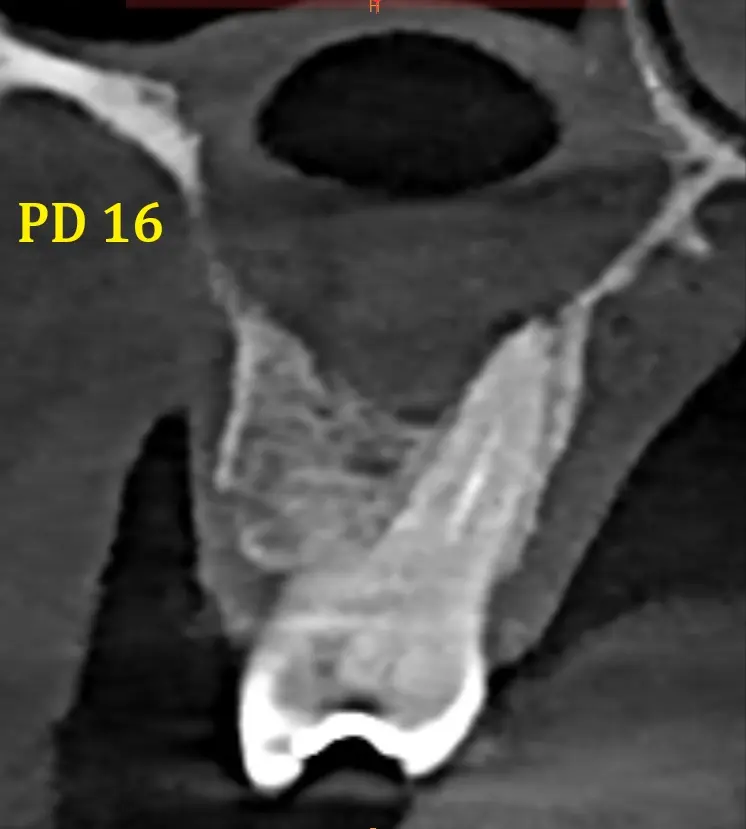

Al realizarle la tomografía se evidencia de manera general dientes con tratamientos de conductos que no llelgan al limite CDC (Ver imagen 1 panorámica). En zona de Pd 16 se ve imágen hipodensa , de carácter expansivo que empuja las zonas adyacentes y el seno maxilar, generando una disminución del reborde óseo tanto palatino como vestibular, se observa que la pieza dental 16 presenta tratamiento de conducto, esta lesión genera también un engrosamiento de la membrana sinusal (posible quiste de retención mucosa) y disminución o posible ausencia del piso sinusal. Sobre la misma se observa en la imagen N°6 que presenta los cortes trasnaxiales, una cavidad de aire en dicho quiste periapical. Posiblemente debido a una interacción con las bacterias sinusales. En la cavidad sinusal se observa el pólipo sinusal de la cavidad derecha.